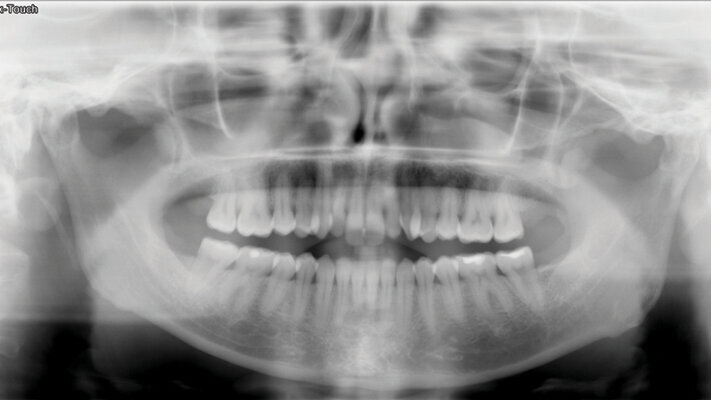

Vstupní foto a RTG dokumentace